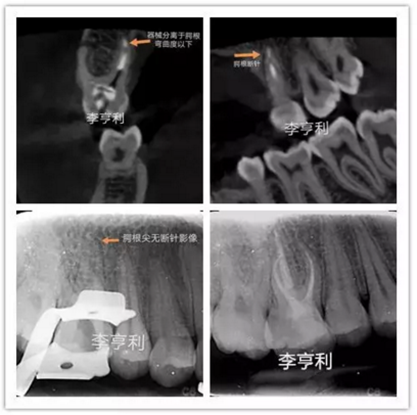

李亨利取出腭尖斷針的病例

在根管治療前,一定要充足地預(yù)估難度,謹(jǐn)記根管解剖,并且要熟悉自己臨床使用器械的設(shè)計、尺寸和參數(shù)。雖然說斷針本身并不影響治療效果,但往往都是因為患者的個人意愿,最后選擇取出斷針。如果難度超過術(shù)者自身的能力,就一定要轉(zhuǎn)診至專科的牙體牙髓醫(yī)生進(jìn)行處理。